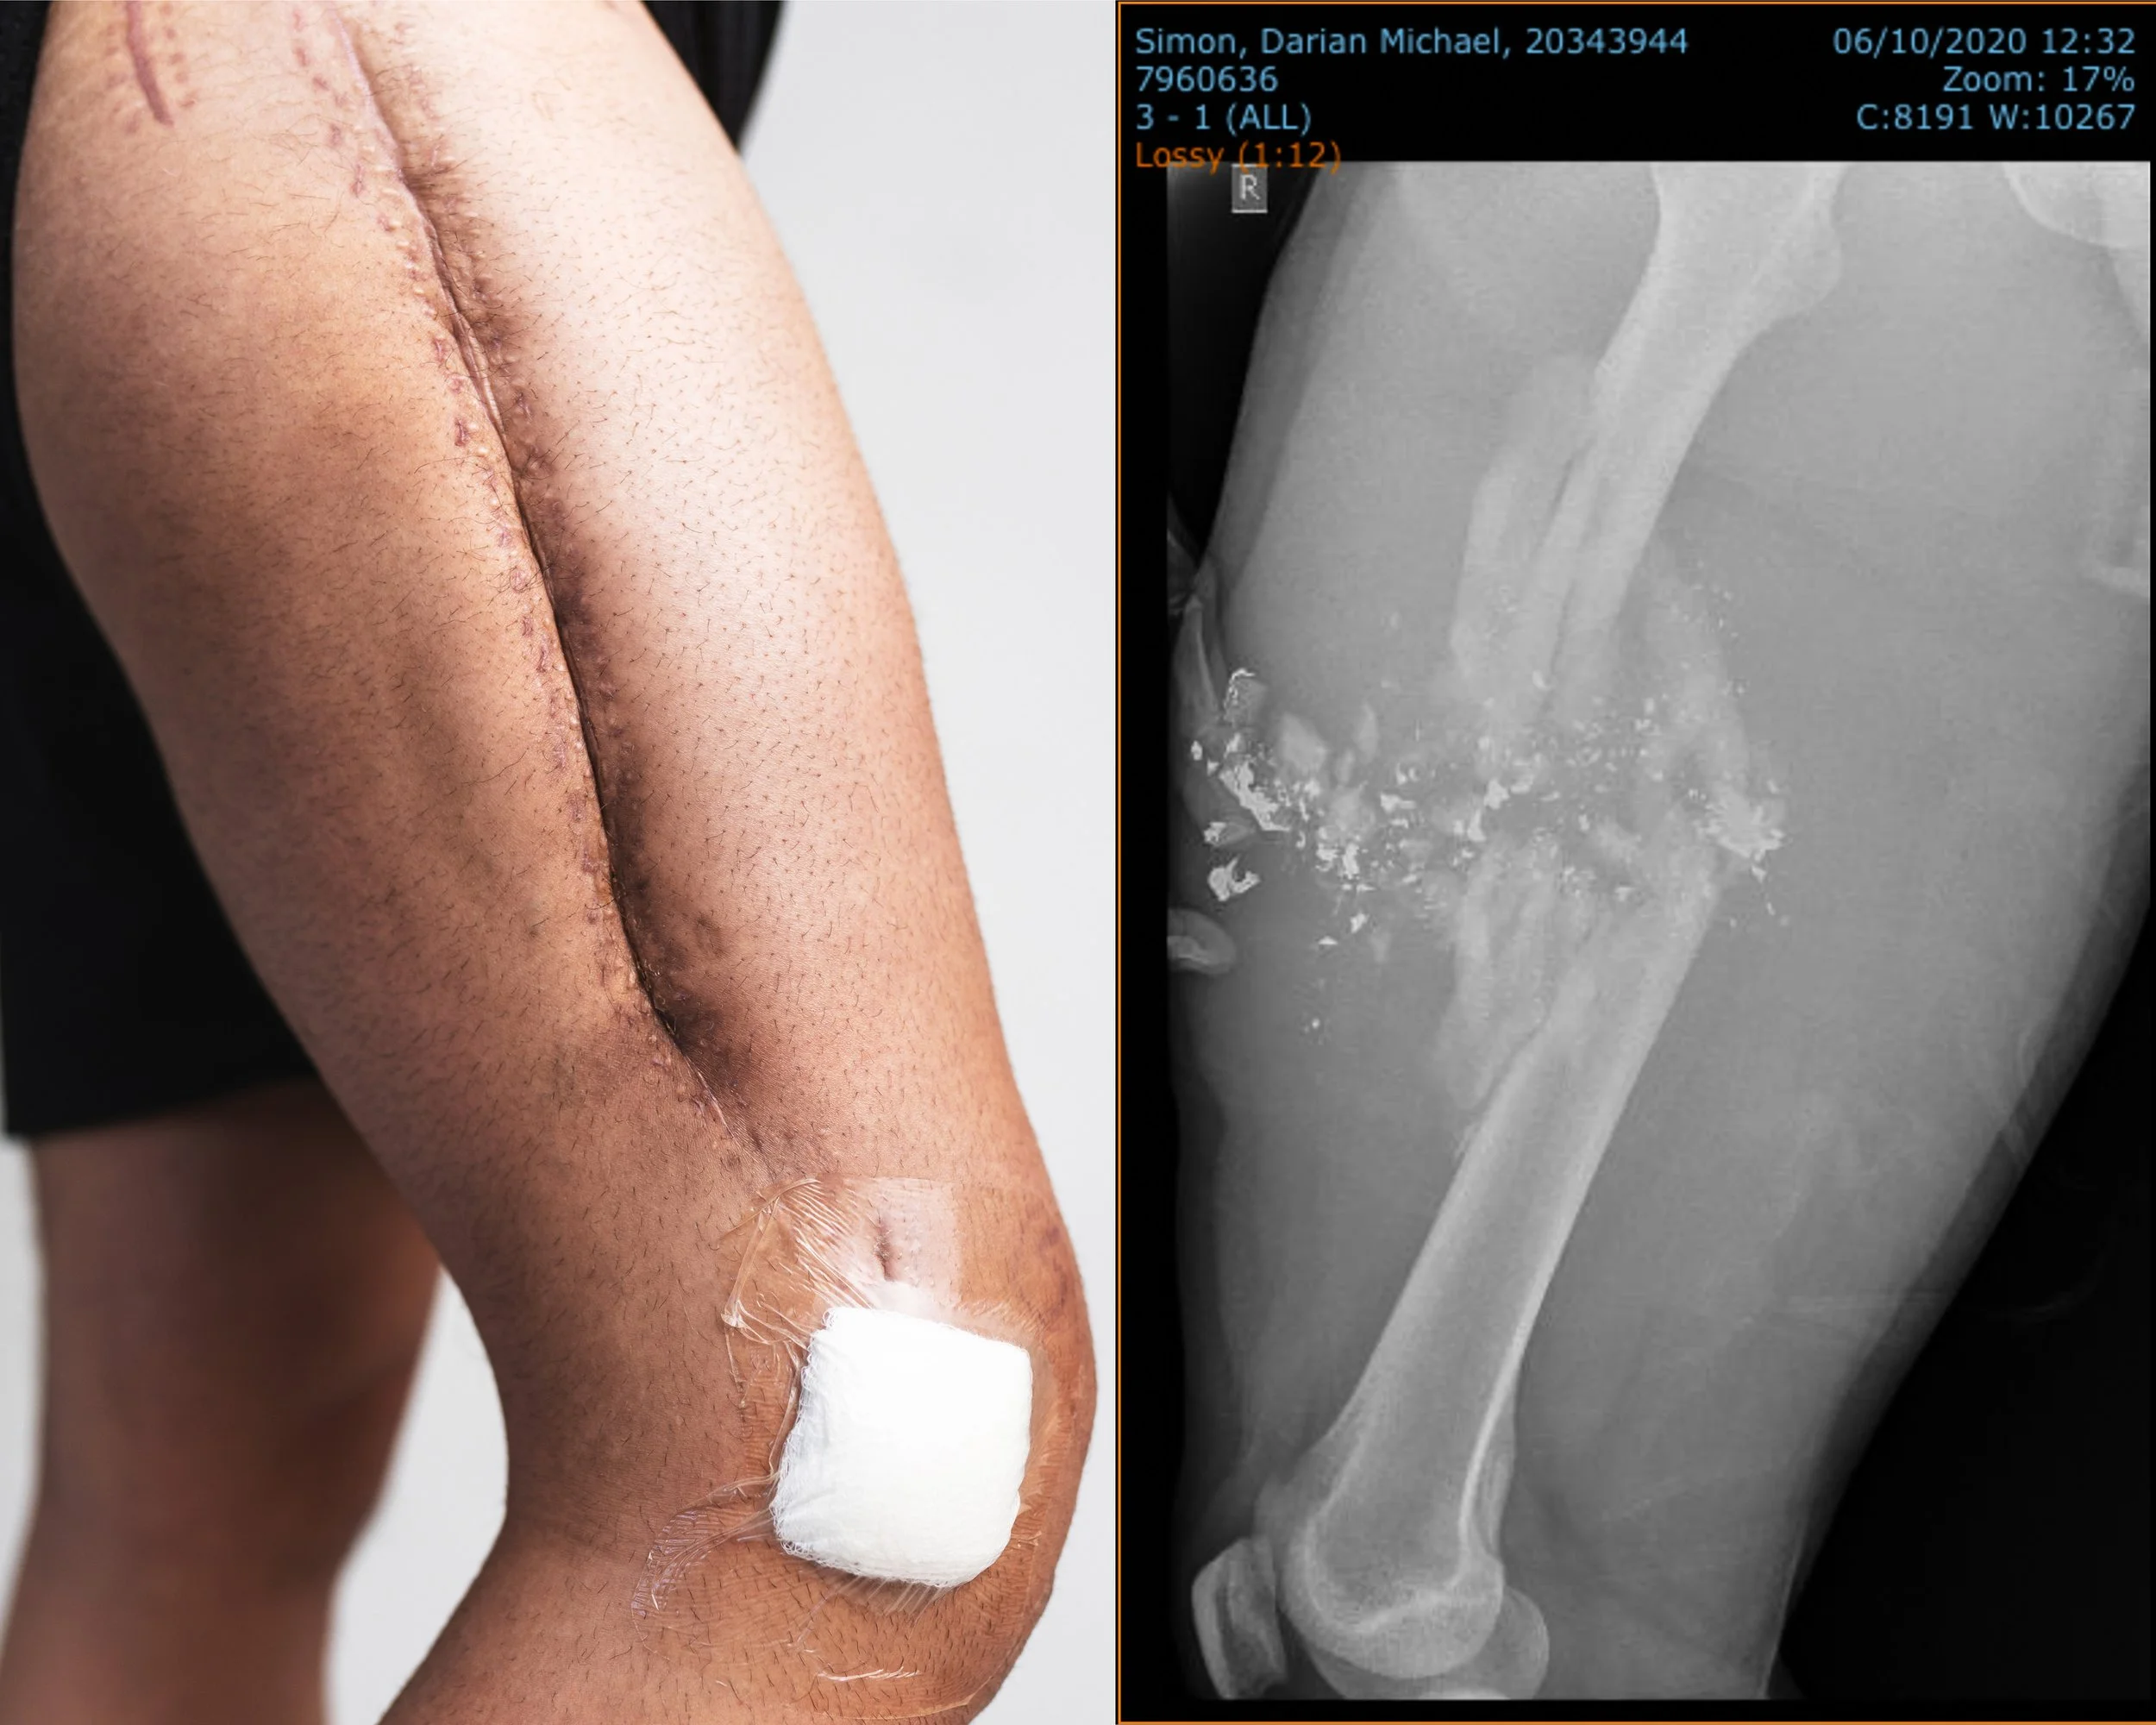

I AM A WARRIOR

I’ve always wanted to photograph my scars someday in hopes to tell a bigger story.

818 days + 8 surgeries later.

A story of struggle and resilience. I’ve wanted to depict how it feels to want to disappear… but be seen at the same time. I’ve wanted to honor this body that I feel self-conscious in every day. And I’ve wanted to do all of this to prove to myself that vulnerability can somehow be strengthening.

Truth be told, after everything happened I was actually shocked that I survived. How bizarre that this was real life, and not some fucked up dream. I consistently told myself… “you could live just one more day and be thankful for that”. And I can honestly say that I’m glad I’ve made it this far.